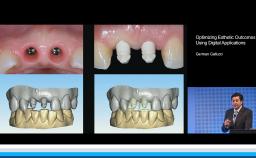

Complications in Regeneration and Reconstruction

Matteo Chiapasco

This lecture reviews in detail the various defects encountered in clinical practice that may need regenerative procedures for hard and soft tissue augmentation. The presentation is supported with excellent visual aids that illustrate how these defects can be reconstructed for prosthodontically driven implant placement. It also addresses how to prevent complications in regenerative and reconstruction procedures as well as the predominant treatment options to manage these complications. Clinical outcomes are supported by reference to several studies and clinical recommendations from the 4th ITI Consensus Conference.